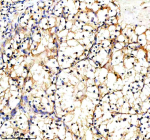

Immunohistochemical staining of PXDN using anti-PXDN antibody. PXDN was detected in a paraffin-embedded section of human renal cancer tissue. Heat mediated antigen retrieval was performed in EDTA buffer (pH 8.0, epitope retrieval solution). The tissue section was blocked with 10% goat serum. The tissue section was then incubated with 2 ug/ml rabbit anti-PXDN antibody overnight at 4oC. Peroxidase Conjugated Goat Anti-rabbit IgG was used as secondary antibody and incubated for 30 minutes at 37oC. The tissue section was developed using an HRP secondary and DAB substrate.